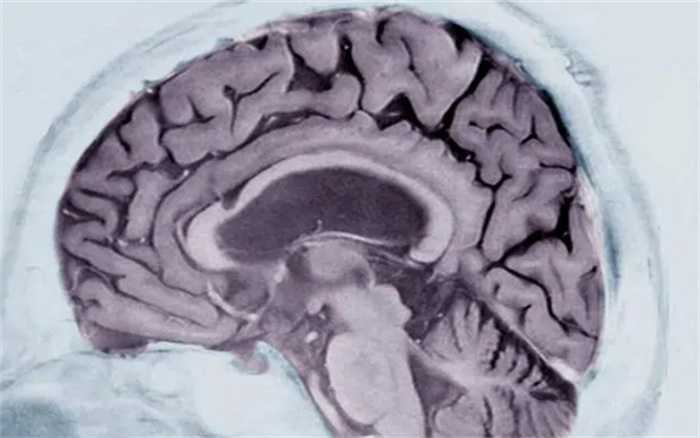

新技术:核磁共振扫描即可确诊阿兹海默症

科学家发明了一套机器学习系统,用这套系统只需分析问诊者的一次脑部核磁共振(MRI)扫描的数据,即可判断其是否患有阿兹海默症。研究者称准确率高达98%。

6月20日发表于《自然》(Nature)旗下的《医学通讯》(Communications Medicine)期刊上的一份研究介绍了一种新的方法,只需问诊者接受一次脑部核磁共振扫描即可完成诊断。

研究称他们借鉴了一套对癌肿瘤分类的算法,修改后用于分析脑部扫描数据。他们把大脑分成115个区域,分别检查这些区域的体积、形态、质地等一共660项特征进行评估,并训练这套机器学习算法找到检查对象脑组织与正常脑组织的差异,从而诊断是否患有阿兹海默症。

研究人员用这套系统分析了400名该病的患者、一些健康人和患有其它类型神经系统疾病患者的数据,查看这套诊断工具的有效性。这400名患者来自阿兹海默疾病神经影像学项目(Alzheimer’s Disease Neuroimaging Initiative),包括了早期和晚期患者;其它类型神经系统疾病的患者包括额颞叶痴呆患者和帕金森病患者。此外,他们还用这套系统检查了80多位正在接受帝国学院医疗保健NHS基金项目诊断的问诊者的数据,对比诊断的结果。

研究称,仅靠这套工具就能确诊其中98%的病患,而且对其中79%的病患,还能分辨出他们的疾病处于早期还是晚期。

这套系统发现了与此病相关的多个脑部区域所出现的变化,有些区域科学家以前不知道与此病相关,比如小脑、腹侧间脑(ventral diencephalon)。这些信息为科学家继续研究此疾病提供了新的线索。